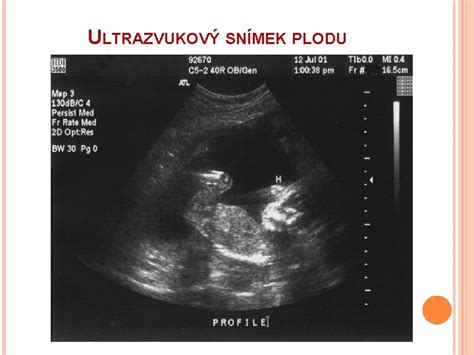

- Ultrazvukové vyšetrenie: Potvrdí vitalitu bábätka, určí gestačný vek aj početnosť tehotenstva.

- Podrobné ultrazvukové vyšetrenie plodu (20. - 22. tt): Slúži na detekciu štrukturálnych a funkčných abnormalít. Lekár detailne kontroluje orgány plodu, placentu, plodovú vodu a rast.